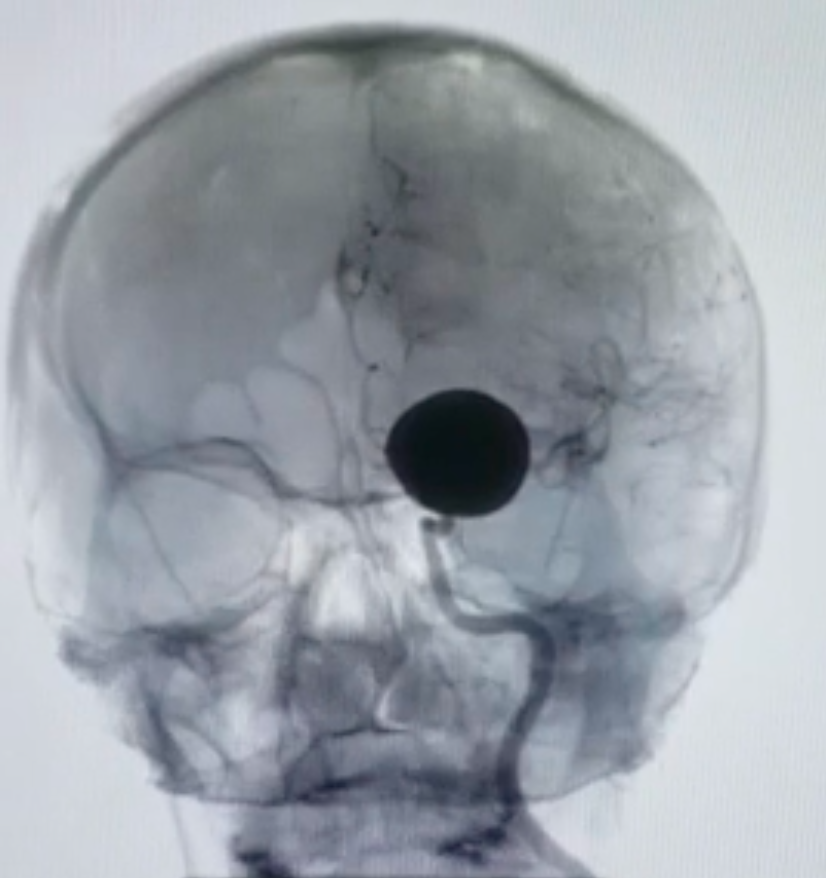

Um aneurisma é uma dilatação anormal que pode ocorrer em vários vasos do corpo, incluindo as artérias que irrigam o cérebro. Eles causam alteração do fluxo sanguíneo no local e constituem um local de fragilidade na parede do vaso, predispondo a ruptura e sangramento. No caso de aneurisma cerebral, ocorre sangramento intracraniano, mais especificamente no espaço subaracnóideo.

O aneurisma cerebral não roto geralmente não causa sintomas, exceto quando é muito grande. Porém, devido ao risco de ruptura, deve ser avaliado quanto à necessidade de tratamento. Está bem estabelecido na literatura que aneurismas acima de 5 milímetros devem ser avaliados para tratamento, caso o paciente tenha condição clínica para tal. Alguns estudos mostram que mesmo aneurismas menores, de 3-5 milímetros, devem ser considerados para tratamento devido ao risco não desprezível de sangramento. Esse tratamento pode ser realizado através de microcirurgia (clipagem) ou por embolização (endovascular). Ambas as possibilidades têm riscos, benefícios e situações onde são mais ou menos indicadas. Ainda não há consenso na literatura médica acerca da melhor abordagem e não é o objetivo desse texto essa discussão.

A ruptura de um aneurisma cerebral ocasiona a hemorragia subaracnóide espontânea (HSAE), quadro gravíssimo com alta morbidade e mortalidade. Geralmente a HSAE se manifesta através de uma dor de cabeça (cefaleia) súbita e intensa. Pode vir acompanhada de perda de consciência, vômitos, rigidez na nuca e sintomas mais graves como fraqueza nos membros e até coma. É considerada uma urgência médica e o paciente deve procurar um pronto socorro o mais rápido possível. Nestes casos, os objetivos do tratamento são a exclusão do aneurisma da circulação (através da clipagem ou embolização) e o tratamento da hemorragia subaracnóide e suas complicações relacionadas.